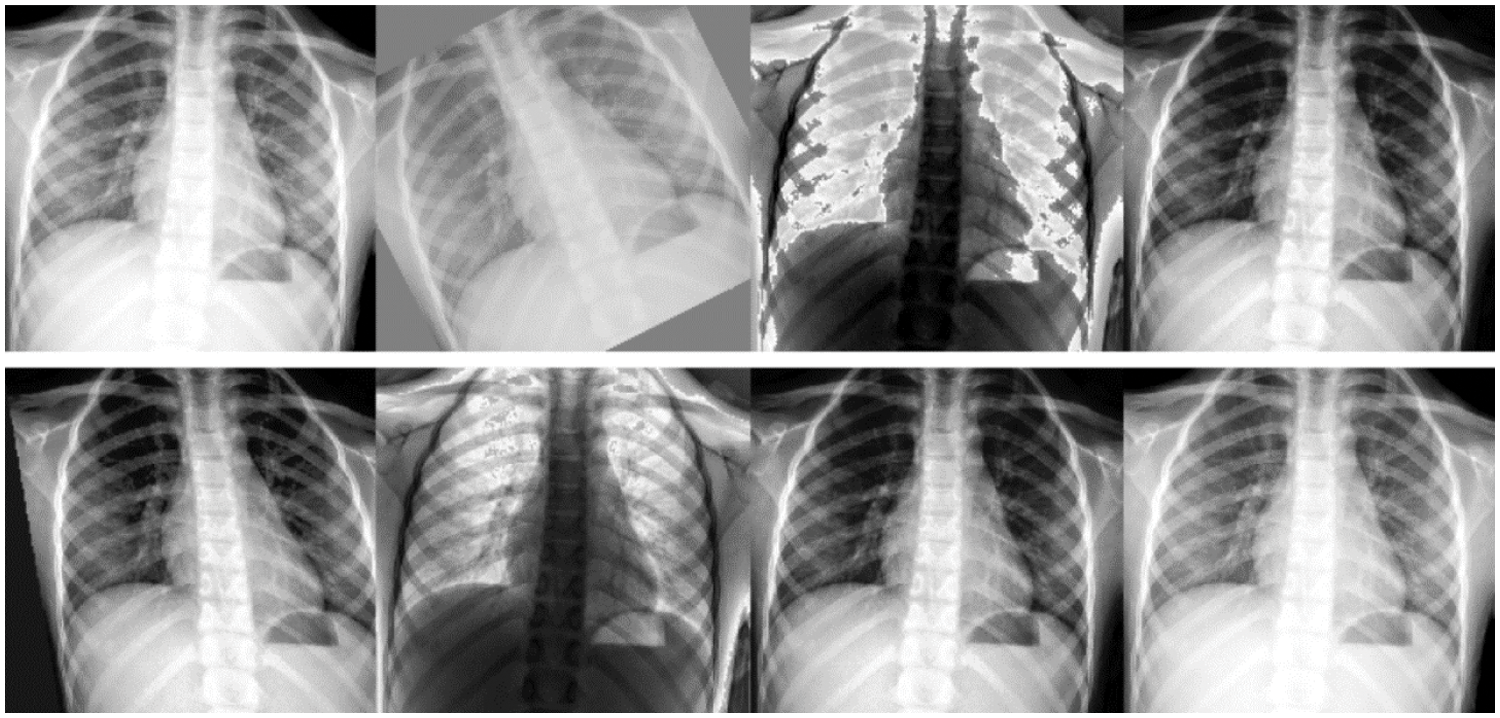

Data augmentation can increase the sample of the training set, effectively alleviate the model overfitting situation and bring stronger generalization ability to the model. After cropping the chest X-ray images, the images were augmented using automated data augmentation. In this research, the augment policy [37], which is trained on the ImageNet, is used for automatic data augmentation. By increasing the data, the diversity of samples, and the performance of the model for the diagnosis of children with pneumonia. Several samples after the automatic data augmentation are shown in Fig. 9.

Figure 9: Several samples with automatic data augmentation